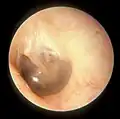

This is a normal left eardrum.

Tympanic membrane viewed by otoscope